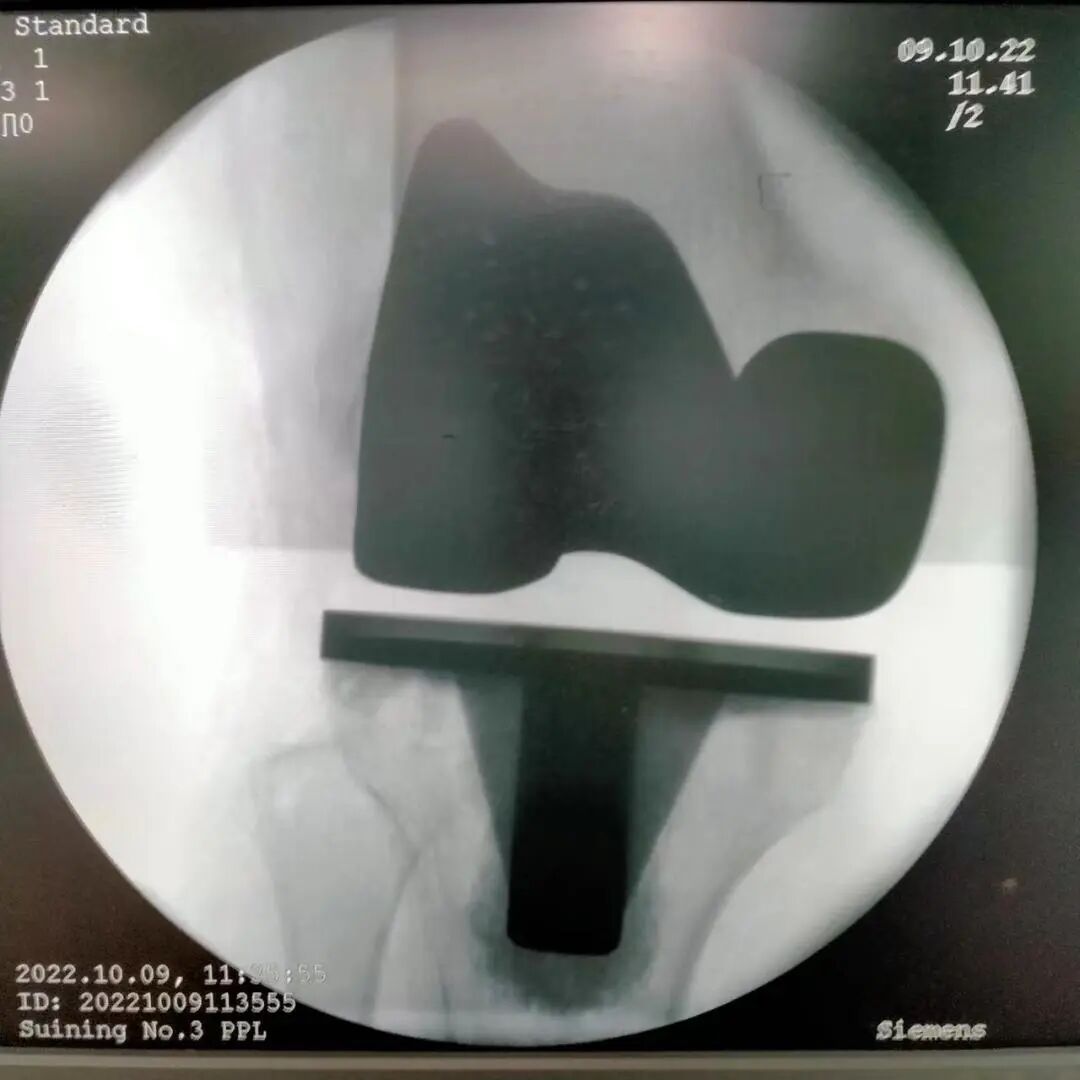

74岁的王奶奶,从十年前,右膝就出现了关节疼痛,近期逐渐加重,站立时感到疼痛难忍,生活质量大大降低。在家人的陪同下,她来到我院骨伤科就诊。主治医师王成接诊后为患者做了DR、CT检查发现,患者右膝骨关节病伴屈曲挛缩,保守的治疗已经很难发挥效果,需进行关节置换。

然而,王奶奶担心手术费用昂贵,犹豫不决。看着满脸愁容的王奶奶,了解原因后,王成笑着告诉她,现在国家有政策,膝关节假体价格大幅度下降,不到万元即可做手术,而且恢复快,术后第二天就可下地活动。在消除种种顾虑后,王奶奶欣然同意手术。

经过手术,王奶奶完全告别了被膝关节折磨的岁月,往日愁容烟消云散。